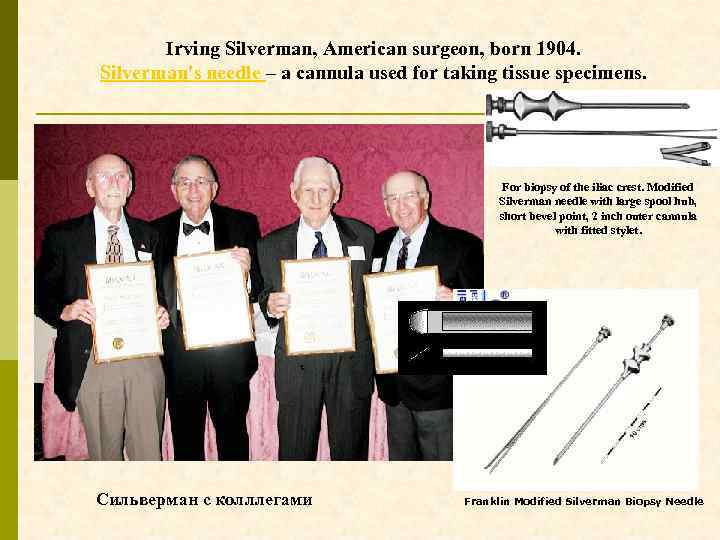

Irving Silverman, American surgeon, born 1904. Silverman's needle – а cannula used for taking tissue specimens. For biopsy of the iliac crest. Modified Silverman needle with large spool hub, short bevel point, 2 inch outer cannula with fitted stylet. Сильверман с колллегами Franklin Modified Silverman Biopsy Needle

ЧТО НУЖНО ДЛЯ ВЫПОЛНЕНИЯ ДИАГНОСТИЧЕСКОЙ НЕФРОБИОПСИИ? Биопсионная игла Vim-Silverman’a игла Tru-Cut игла с пружиной Аппарат ультразвуковой диагностики (с ультразвуковой поддержкой нефробиопсия выполняется быстрее, но частоту осложнений она не уменьшает) А также: шприц 10– 20 мл, игла для п/к введения анестетик (новокаин 0, 5% 20– 40 мл) игла инъекционная 100– 120 мм скальпель предметное стекло консерванты для биоптата (N 3 !!)